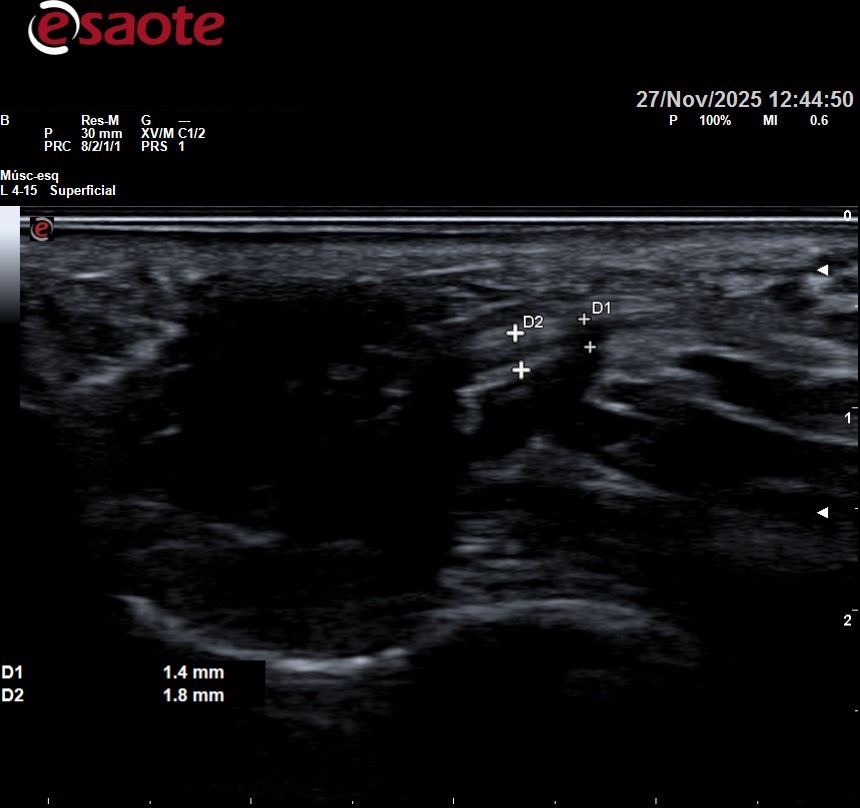

Se puede observar arriba la ecografía de una paciente con neuroma de morton entre tercer y cuarto metatarsiano sintomatológico, que posteriormente se infiltró. Se observa como desde lo metatarsianos hacia los dedos el nervio se va haciendo más gordo. En la foto de abajo a la derecha lo vemos a lo largo en esa zona negra circular que se observa de la mitad de la imagen hacia la izquierda.

Infiltración con ecógrafo de un neuroma de mortón. Se observa como en todo momento controlamos la aguja y donde queremos llegar con ella para ser lo más precisos posibles en el tratamiento, asegurandonos un correcto resultado.